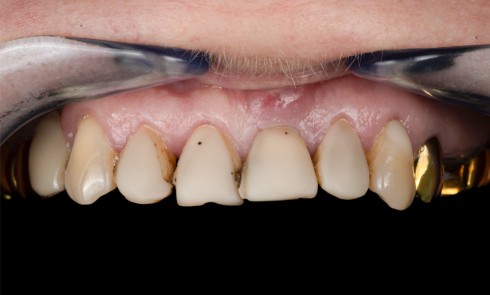

Prothèse implantaire, temporisation et restauration de la mastication et du sourire chez une patiente bruxomane

Quels sont les problèmes posés par le bruxisme ? Comment peut-on placer des implants sur un patient bruxomane ? Pourquoi utiliser un articulateur adaptable ? Comment mener la chronologie du traitement ?